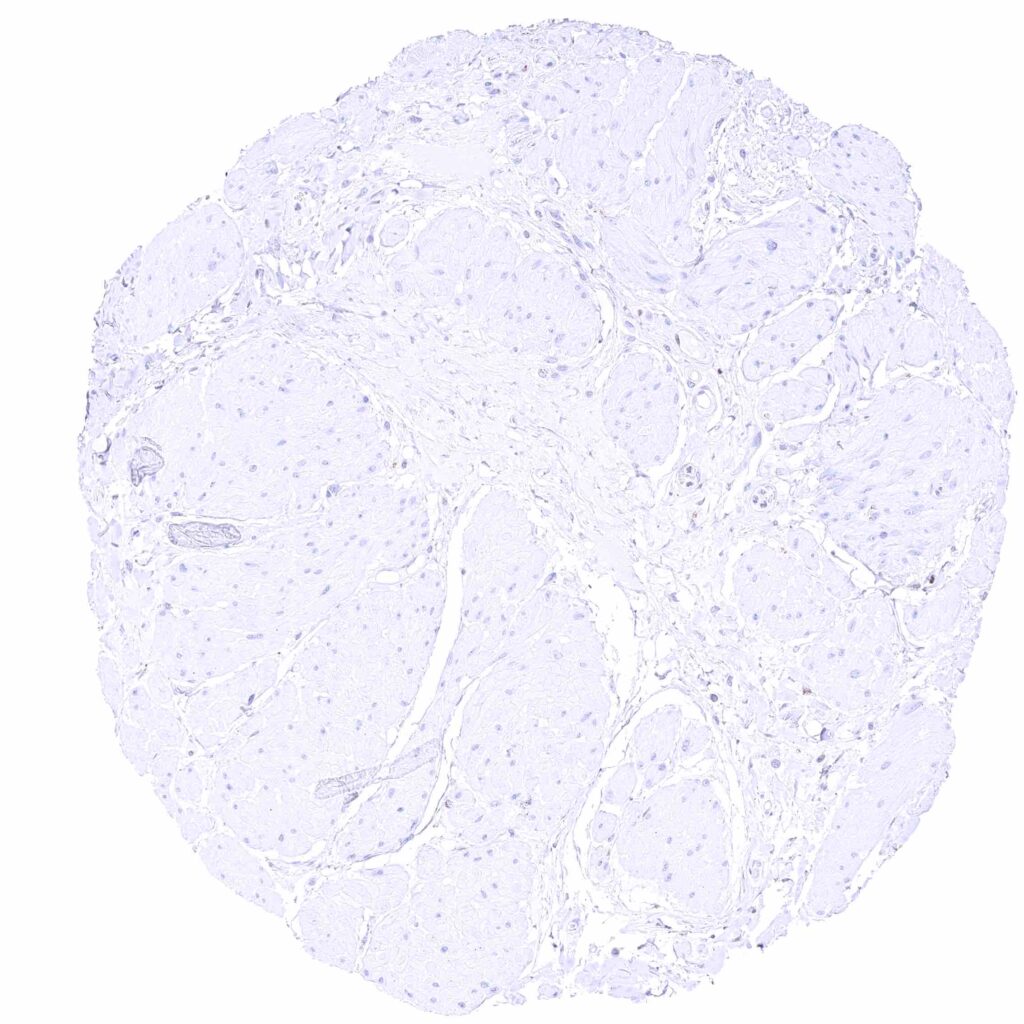

Urinary bladder, muscular wall